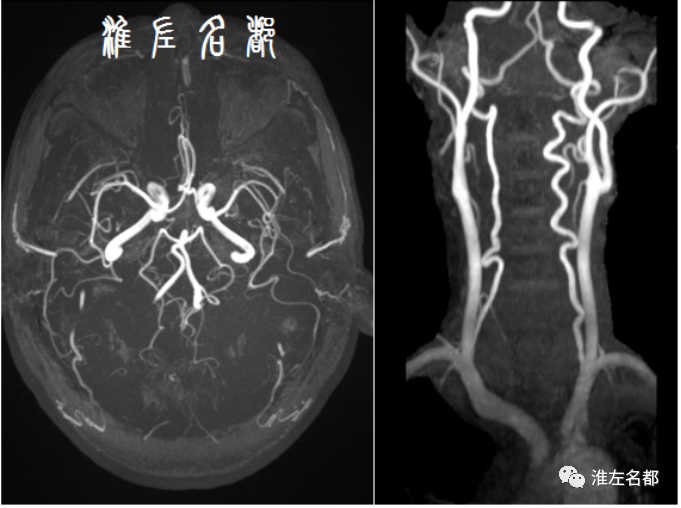

伴随科技发展,近半个世纪以来,多种先进技术,尤其是血管影像技术,被应用于脑血管病变的诊断评估,极大促进了该领域的发展。目前常规应用于脑血管病变评估的影像技术包括:DSA、CTA和MRA,这些技术主要通过显示血管腔的异常进行血管病变的评估,如狭窄、闭塞、动脉瘤、血管畸形等病变,其中以DSA的诊断准确性最高,常被奉为“金标准”,缺点是有创操作,有潜在风险。

脑供血动脉系统解剖复杂,按管径来说,分为大血管、中血管和小血管;以颅骨为界,分为颅外和颅内脑动脉;以硬脑膜为界,分为硬膜内和硬膜外动脉。按脑供血区的差异,分为前循环和后循环脑动脉,前循环又分为左右两侧,前后循环和左右前循环通过WILLIS环相连接。当主要脑动脉发生严重狭窄或闭塞病变时,WILLIS环是相当重要的侧支循环代偿途径,然而其存在诸多变异。